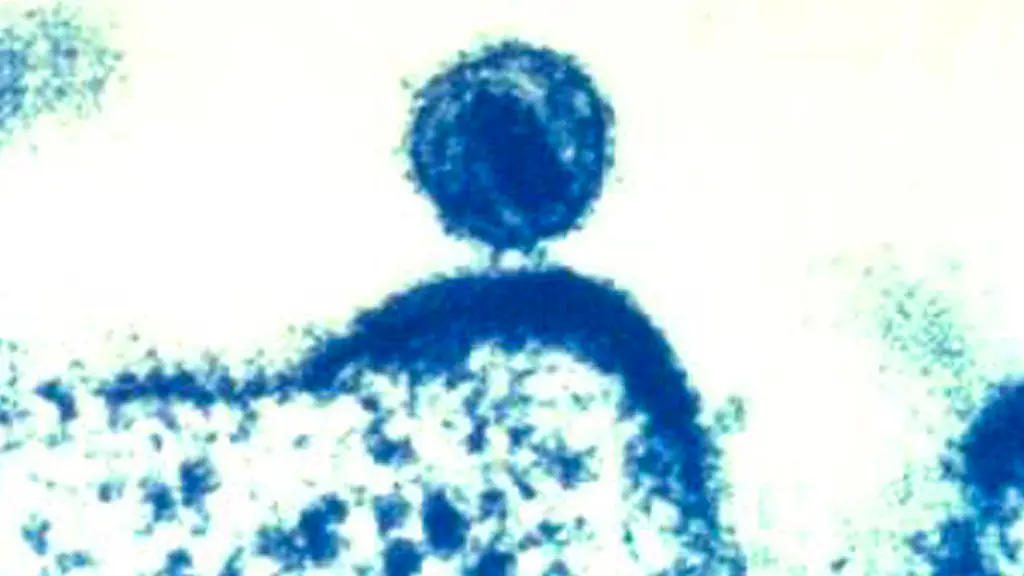

Australien könnte das erste Land werden, das die HIV-Epidemie besiegt. Im vergangenen Jahr werden dort nur noch 555 Neu-Infektionen registriert. Die Herausforderung bestehe darin, diesen Erfolg überall auf der Welt zu wiederholen, meinen Experten.

Laut der University of New South Wales wurden in Australien 2022 nur noch 555 neue HIV-Infektionen verzeichnet. Zum Erfolg hätten vor allem vorbeugende Maßnahmen wie verstärkte HIV-Tests und die Präexpositionsprophylaxe beigetragen. Diese ist für bestimmte Menschen in Australien - wie auch in Deutschland - auf Rezept mit kleiner Zuzahlung erhältlich. Dabei nehmen HIV-negative Menschen ein Medikament ein, um sich vor einer Ansteckung mit dem Virus zu schützen. Zudem kann dank der heutigen medizinischen Möglichkeiten immer besser verhindert werden, dass eine HIV-Infektion zur Immunschwächekrankheit Aids wird.